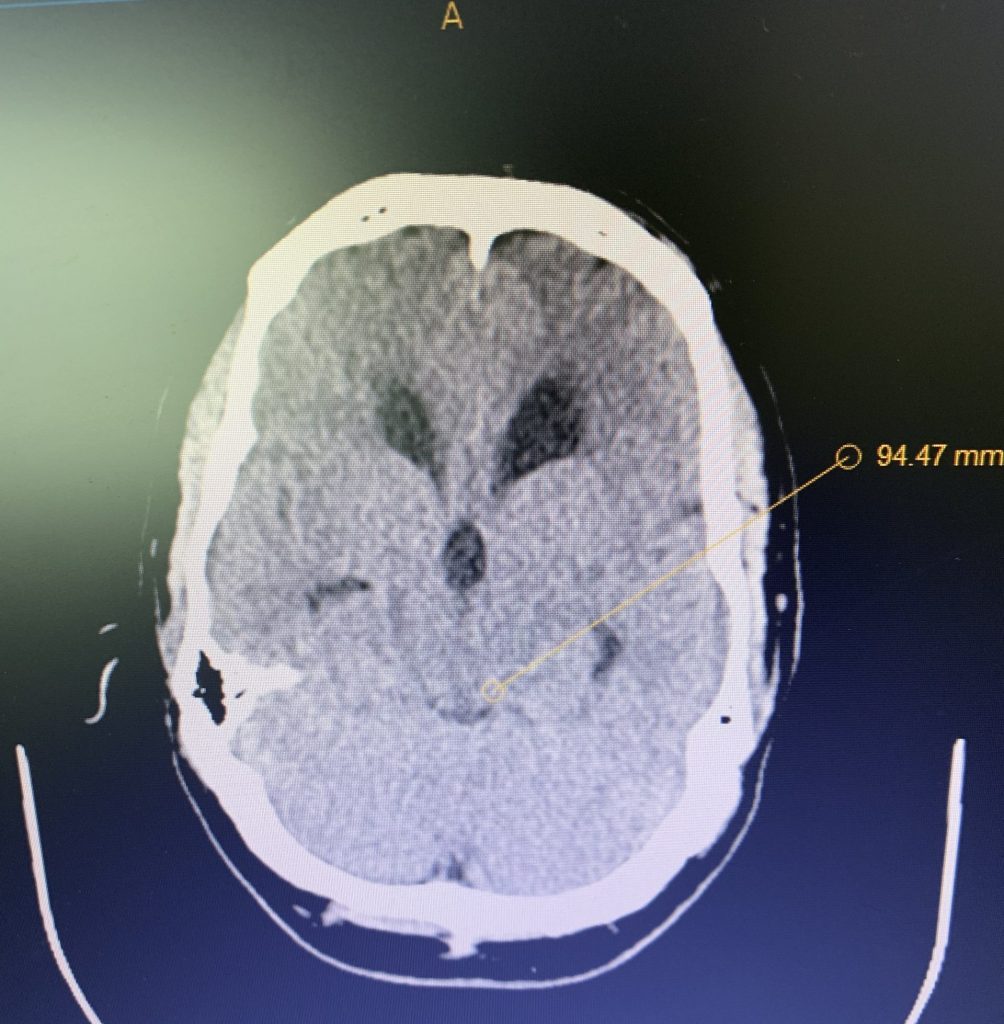

Brain:

Neurosurgeons Collaborate to Treat Giant Symptomatic Meningioma

Author: Ramin Rak M.D., F.A.A.N.S., F.C.N.S., Jonathan L. Brisman M.D., F.A.C.S., Read More!